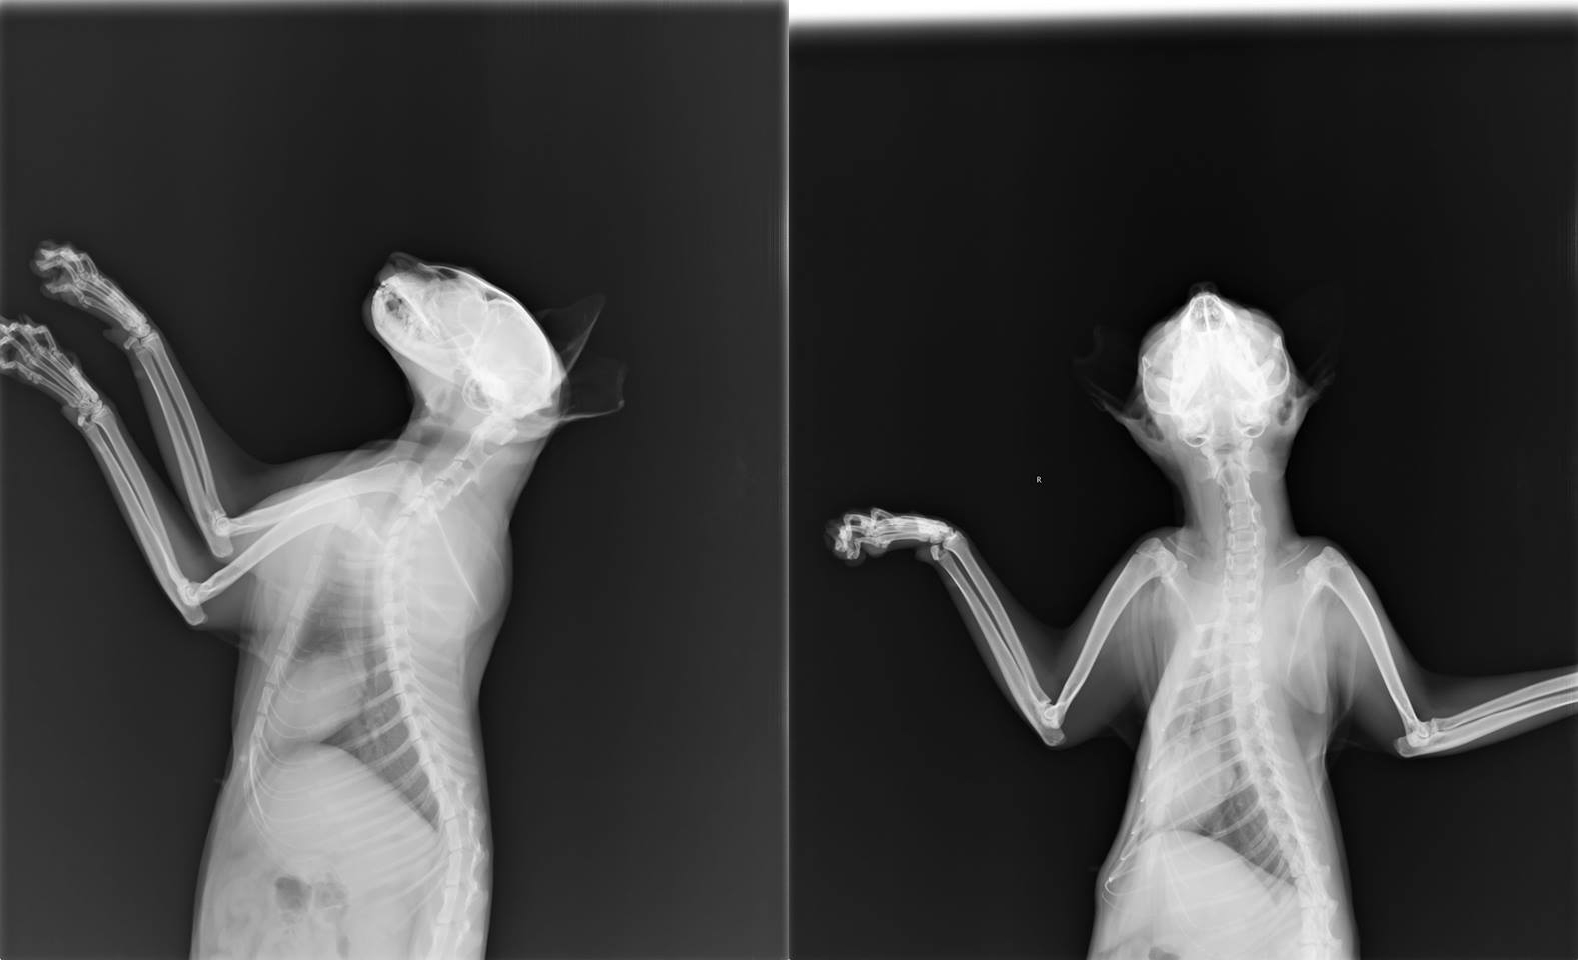

7/10照X光確認無異物卡在傷口深處,詳細檢查傷口後,是深處之流膿未清除乾淨,另外傷貓耳疥感染嚴重,認為傷口應為自行抓傷非外力造成,因重複抓傷造成感染膿腫,進行情創及局部縫合,並且施打治療耳疥針